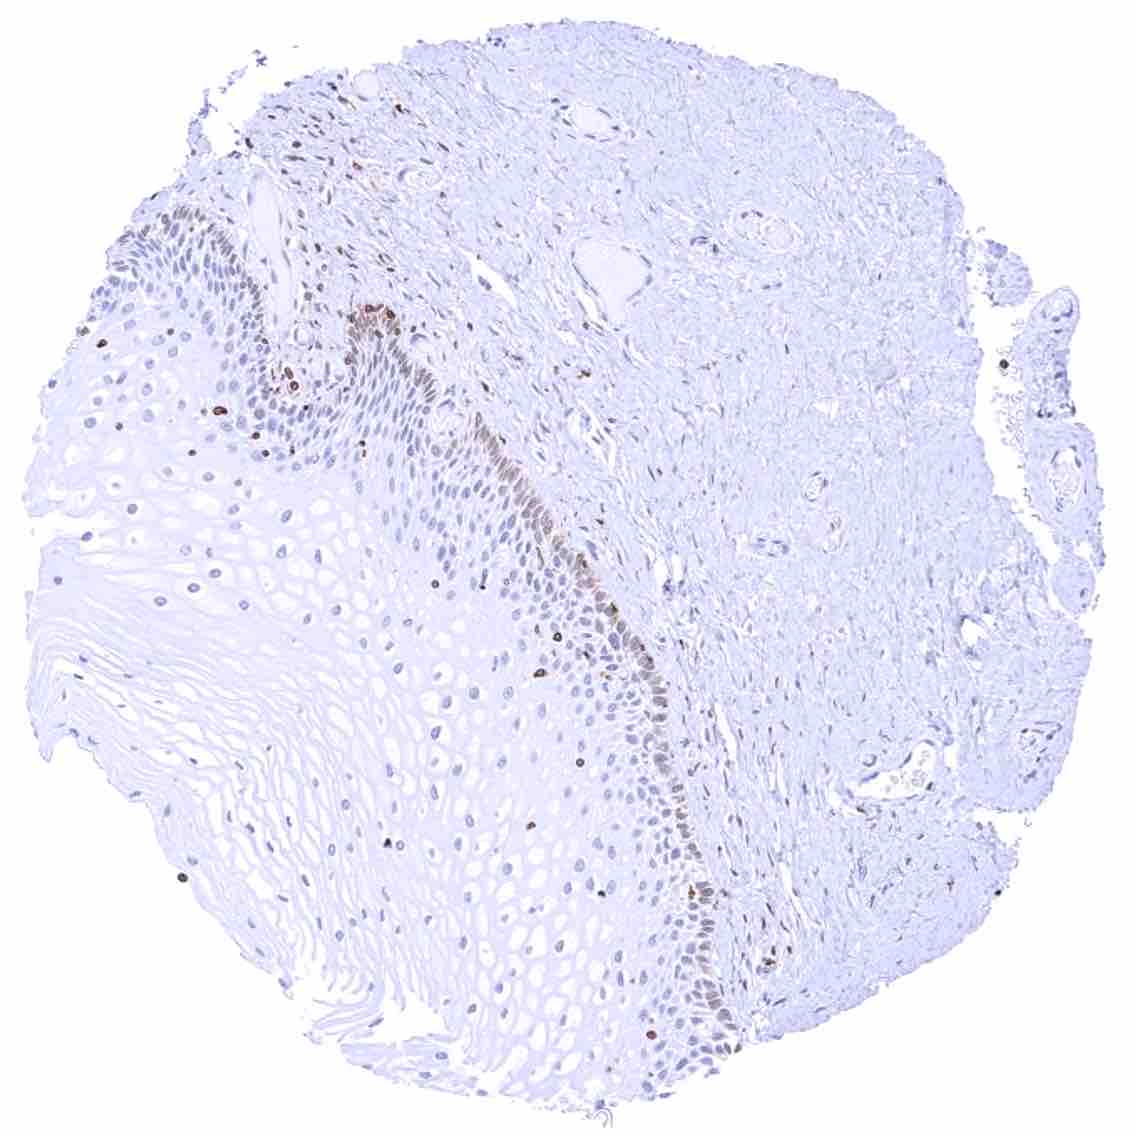

Uterus, ectocervix – Strong cytoplasmic bcl-2 staining of basal cells of the squamous epithelium in this sample.

Uterus, ectocervix – Weak cytoplasmic bcl-2 staining of basal cells of the squamous epithelium.